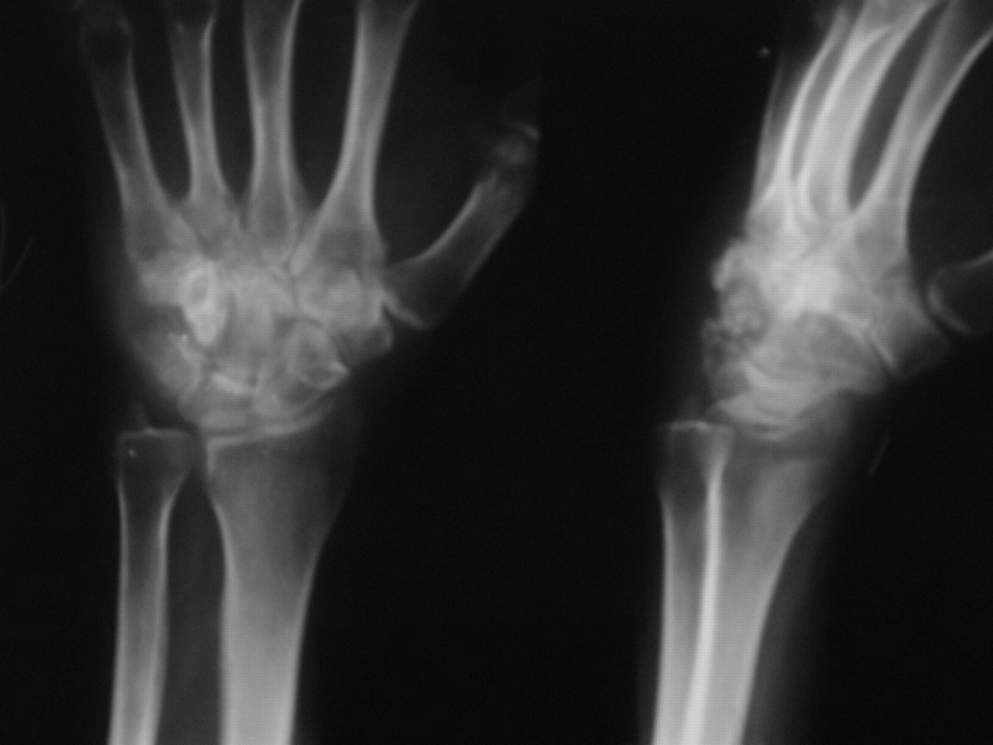

Из анамнеза:около 1,5лет назад смутно отмечает травму левой кисти (ударилась тылом левой кисти),значения не придала,за медицинской помощью не обращалась.Боли не беспокоили.После травмы -беременность,нормальные роды.За месяц до родов больную стали беспокоить боли в области левого кистевого сустава,ограничение движений в кистевом суставе.В мае 2007г при осмотре-стойкая контрактура кистевого сустава в положении умеренной ладонной флексии.Гиперестезия кожных покровов тыла кисти,лёгкое,преходящее онемение пальцев левой кисти.Пальпация кистевого сустава резко болезнена.На рентгенограммах(прилагаются)очаг деструкции в области крючковидной кости с свободно лежащим фрагментом костной плотности.

Больная направлялась в областной центр(где консультирована онкологом,тубостеологом,проводилось СКТ(снимков к сожалению не имею,остались в областной больнице)Инцизионная биопсия мягких тканей и костей запястья)Гистология-между костными балками очаговая инфильтрация с примесью единичных лейкоцитов,участки некроза костной ткани,участки фиброзно-мышечной ткани с очаговым воспалением.Проводилось протиовоспалительное лечение-без существенного эффекта.Через 5 месяцев больная вновь появилась в поле зрения,клиническая картина та же,рентгендинамики практически никакой.

Приношу извинение за качество снимков,если получится плохо,попробую обработать ещё раз и выслать.С уважением Александр